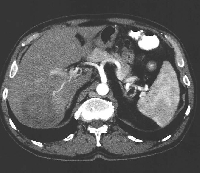

Δεξιά πλάγια ηπατεκτομή για συμπτωματικό φλεγμονώδη ψευδοόγκο

Πρόκειται για άνδρα ασθενή 50 ετών, ο οποίος υποβλήθηκε σε αξονική τομογραφία άνω κοιλίας στα πλαίσια διερεύνησης πυρετού αγνώστου αιτιολογίας. Βρέθηκε μάζα στο 6ο και 7ο ηπατικό τμήμα (εικόνα 1). Δε διαπιστώθηκε κίρρωση. Η διερεύνηση για πιθανή πρωτοπαθή εστία εκτός ήπατος ήταν αρνητική. Τέθηκε η διάγνωση της πρωτοπαθούς ηπατικής μάζας (HCC vs CCa vs άλλη). Οδηγήθηκε στο χειρουργείο και ύστερα από διενέργεια διεγχειρητικού υπερήχου για καθορισμό του επιπέδου ηπατικής διατομής (εικόνα 2), υποβλήθηκε σε δεξιά πλάγια ηπατεκτομή (εικόνα 3). Το ηπατικό κολόβωμα (εικόνα 4) υπολογίστηκε στο 72% του αρχικού μεγέθους του οργάνου. Στο παρασκεύασμα (εικόνα 5) βρέθηκε μάζα μεγέθους 6,5 εκατοστών με ιστολογικά χαρακτηριστικά φλεγμονώδους ψευδοόγκου. Ο ασθενής έλαβε εξιτήριο την 6η μετεγχειρητική ημέρα. Έκτοτε παραμένει ασυμπτωματικός (απύρετος).